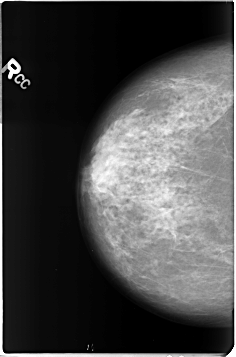

Digital Database for Screening Mammography

Volume: benign_04 Case: B-3361-1

B_3361_1.RIGHT_CC

RIGHT_CC LINES 4632 PIXELS_PER_LINE 3064 BITS_PER_PIXEL 12 RESOLUTION 50 NON_OVERLAY